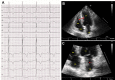

Cardiac Myxoma in a Patient With Hypertrophic Cardiomyopathy

We report a rare case of concomitant hypertrophic cardiomyopathy and cardiac myxoma without LEOPARD syndrome. Additionally, 6 similar cases were systemically reviewed, and the characteristics of this first-ever studied patient group were summarized. (Level of Difficulty: Beginner.).